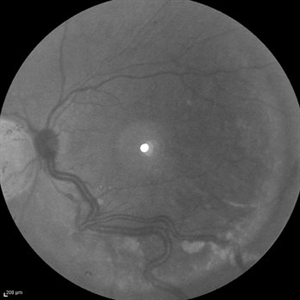

Behcet's Disease Behcet's DiseaseMar 13 2013 by Hamid Ahmadieh, MD Infrared image of the right eye of a 23-year-old man with retinal vasculitis and branch retinal vein occlusion (BRVO) due to Behcet's disease . Photographer: Solmaz Shahmohammad, Negah Eye Center, Tehran Imaging device: Heidelberg Spectralis Condition/keywords: branch retinal vein occlusion (BRVO), infrared image, retinal vasculitis